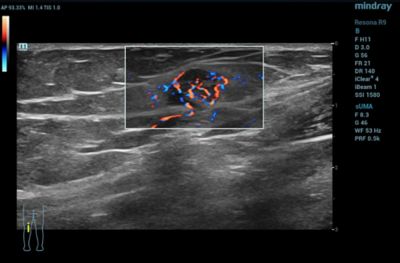

Musculoskeletal

CDI may be used to visualize rheumatological changes in diseased joints and can provide diagnostic information for assessing damage to tendons and ligaments.

Color Doppler Imaging of Musculoskeletal Lesion